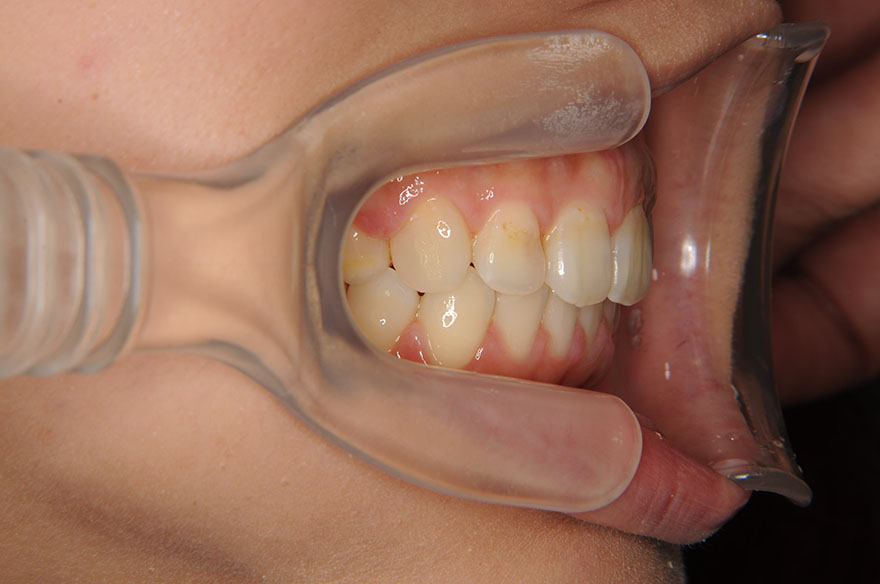

症例2(上顎前突・過蓋咬合)

- ご要望・問題点出っ歯を治したい

- 症状上顎前突・過蓋咬合

- 患者さま情報26歳1ヵ月 女性

- 治療期間2年8ヵ月

- 治療費1,260,000円(税込)

【内訳(別途消費税)】

矯正装置料:900,000円 / 検査診断料:50,000円 / 歯科矯正用アンカースクリュー:10,000円 / 調整料:6,000円 / 保定観察料:3,000円など - 治療詳細上顎リンガル(舌側装置)、下顎ラビアル(表側装置)ブラケット使用。上顎両側4番と下顎左右の親知らずを抜歯。

- リスク・副作用噛み合わせを長期間安定させるためには、保定治療が大切です。